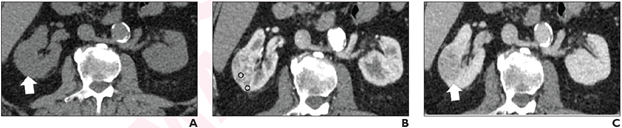

72-year-old man with right interpolar 3.2-cm renal mass. Axial CT images in the (A) unenhanced, (B) corticomedullary, and (C) nephrographic phases at the same level depict the mass (arrow, A and C), which shows avid heterogeneous enhancement. Circular ROIs were placed in the most enhancing component of the mass and in ipsilateral renal cortex (circles, B), to determine the mass-to-cortex corticomedullary attenuation ratio. Heterogeneity scores were assigned subjectively using a 5-point Likert type-scale. These two features were used to inform development of the CT score. In this patient, the mass showed avid enhancement (mass-to-cortex corticomedullary enhancement ratio >0.75) and was considered completely heterogeneous (heterogeneous score, 5) by both radiologists, resulting in CT score 5. Nephrectomy revealed clear-cell renal cell carcinoma.

June 30, 2022 — According to ARRS’ American Journal of Roentgenology (AJR), a 5-tiered CT scoring algorithm may represent a clinically useful tool for diagnosis of clear-cell renal cell carcinoma (RCC) in small (≤4 cm) solid renal masses.

“A 5-tiered renal CT algorithm, including mass-to-cortex corticomedullary attenuation ratio and heterogeneity score, had substantial inter-observer agreement, moderate AUC and PPV, and high NPV for diagnosing clear-cell RCC,” concluded Nicola Schieda from the department of medical imaging at Canada’s Ottawa Hospital.

Schieda and colleagues’ study included 148 patients (mean age, 58 years; 73 men, 75 women) with 148 small (≤4 cm) solid (>25% enhancing tissue) renal masses that underwent renal-mass CT (unenhanced, corticomedullary, and nephrographic phases) before resection between January 2016 and December 2019. Two radiologists independently evaluated CT examinations and recorded calcification, mass attenuation in all phases, mass-to-cortex corticomedullary attenuation ratio, and heterogeneity score (5-point Likert scale, assessed in corticomedullary phase).

Ultimately, Schieda et al’s 5-tiered CT scoring algorithm—including mass-to-cortex corticomedullary attenuation ratio and heterogeneity score—had substantial interobserver agreement (weighted kappa=0.71) and achieved AUC for diagnosing clear-cell RCC of 0.75 (95% CI, 0.68-0.82) for reader 1 and 0.72 (95% CI, 0.66-0.82) for reader 2.

“If validated,” the authors of this AJR article acknowledged, “the CT algorithm may represent a useful clinical tool for diagnosing clear-cell renal cell carcinoma.”